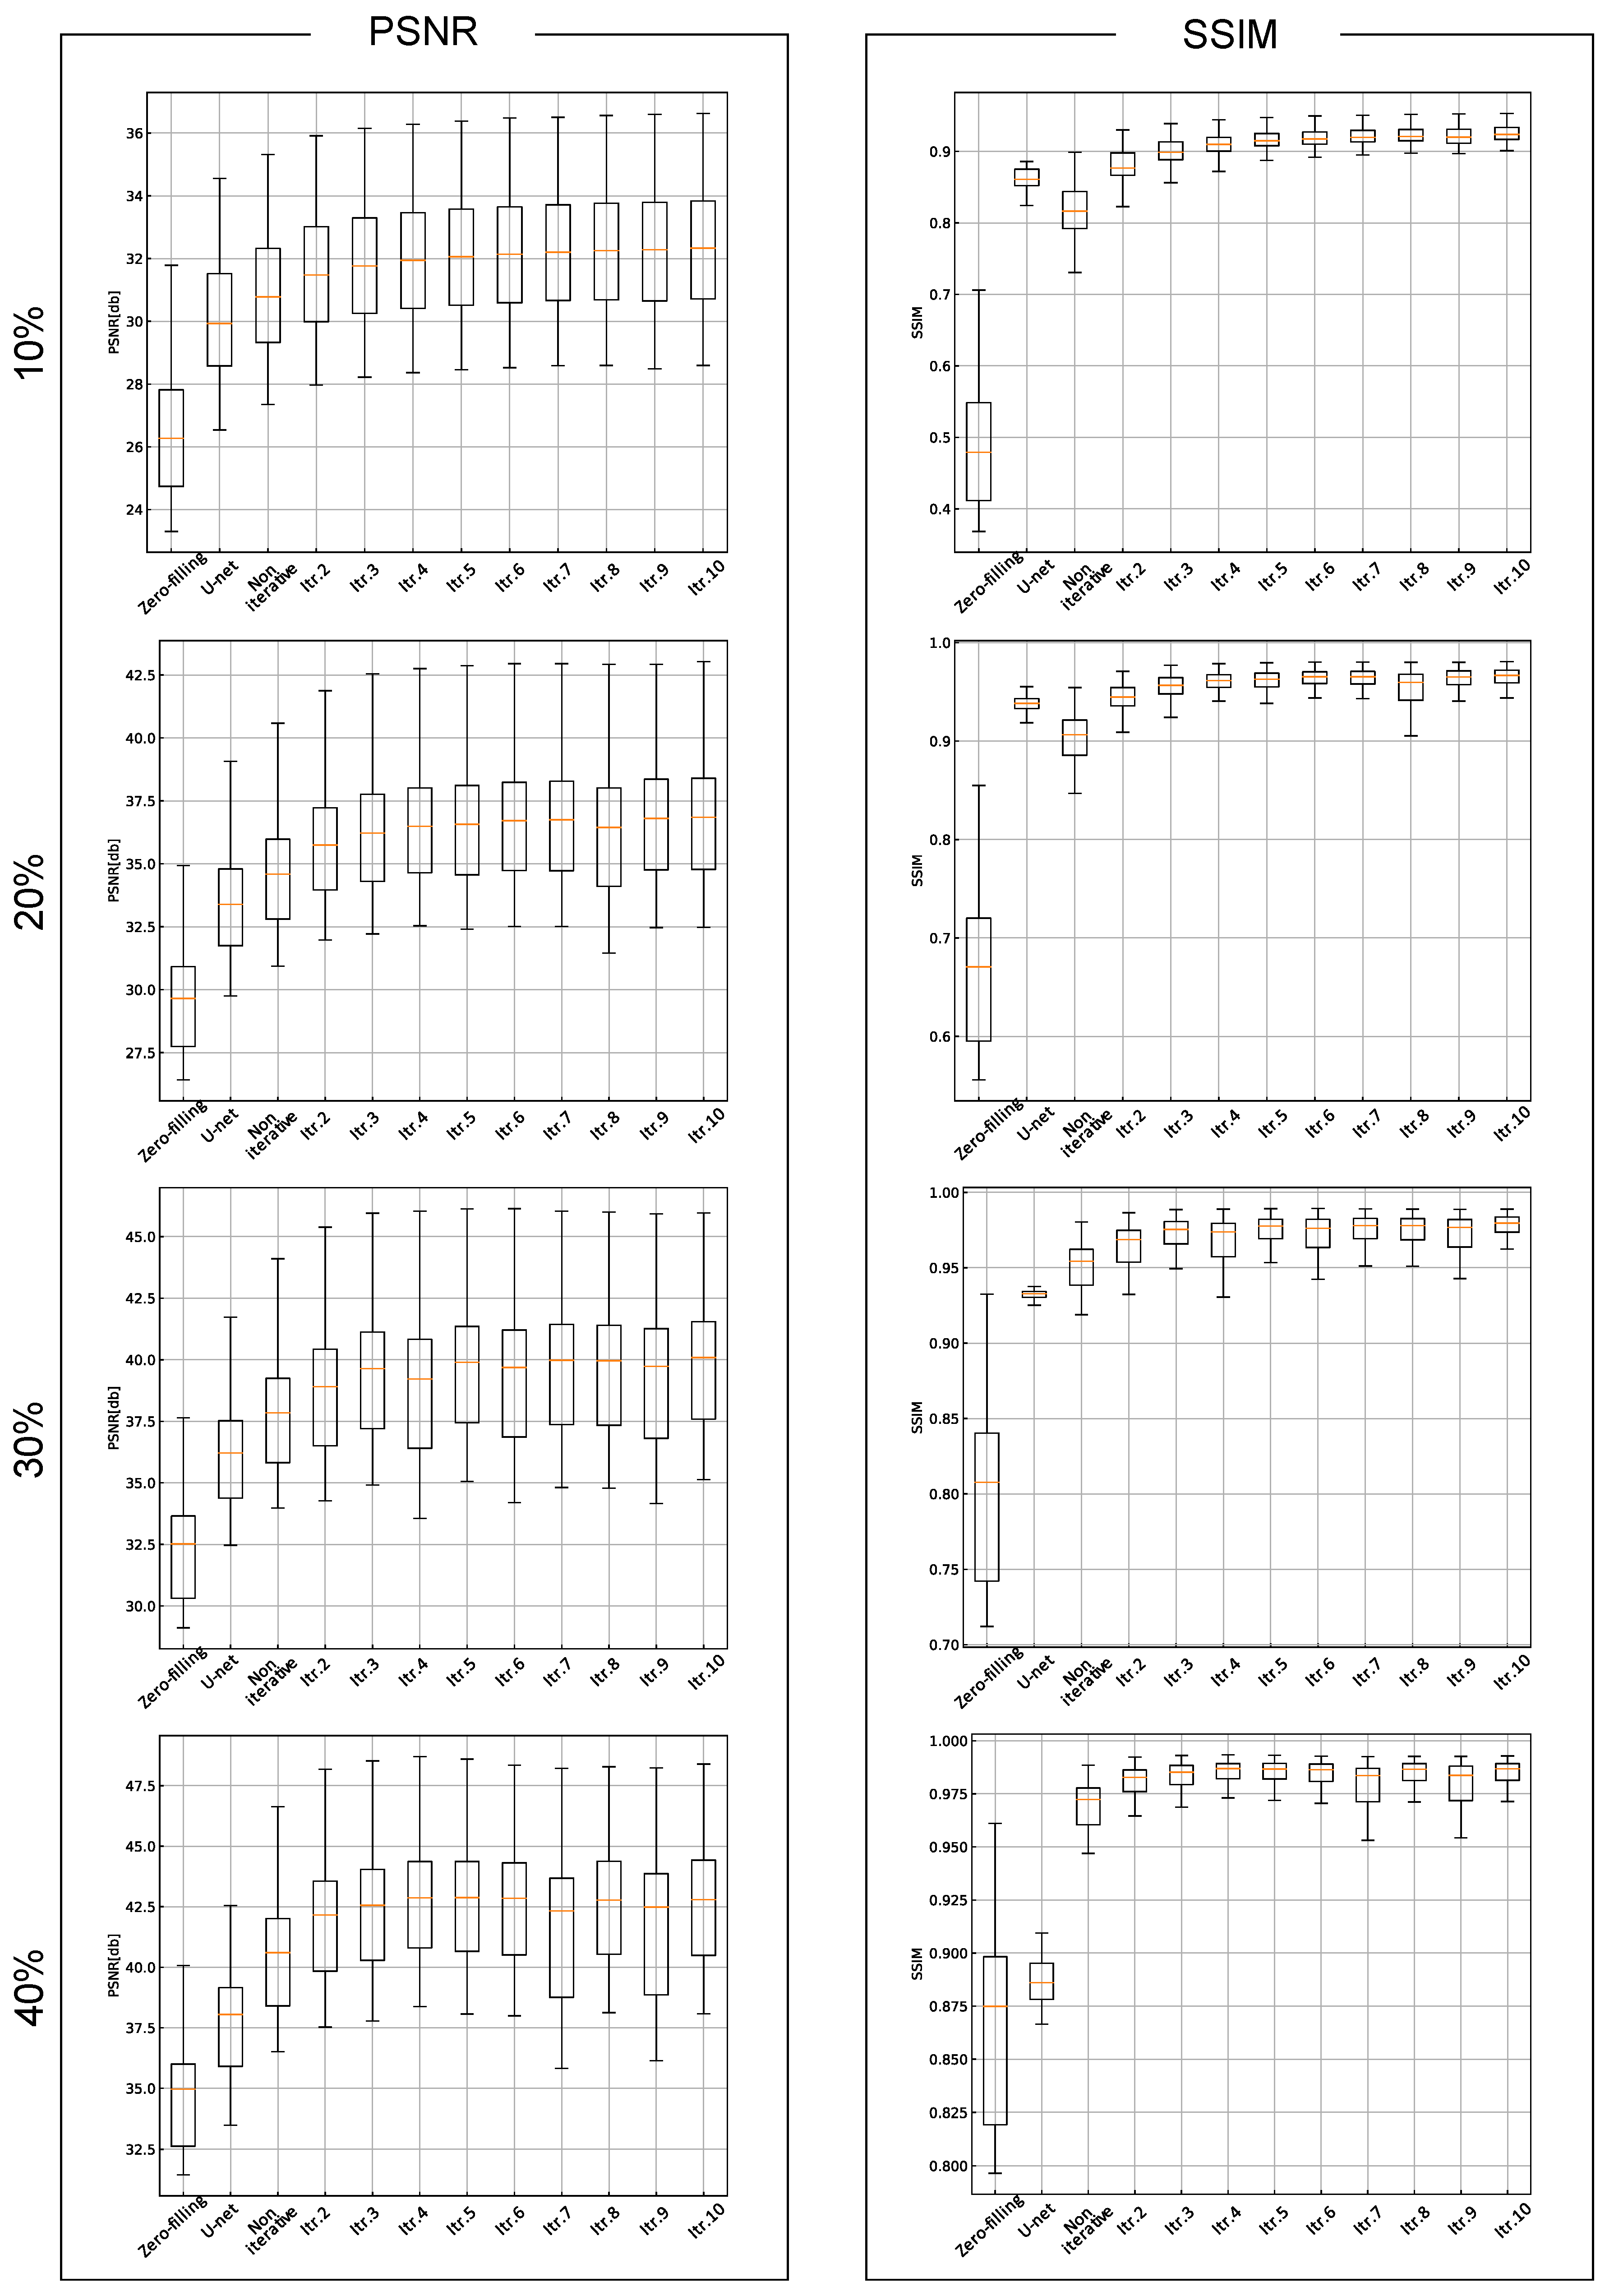

3. Results

| Cartesian Sampling | Radial Sampling | |||

|---|---|---|---|---|

| PSNR (dB) | SSIM | PSNR (dB) | SSIM | |

| Zero-filling | 26.31 ± 2.13 | 0.717 ± 0.040 | 26.45 ± 2.16 | 0.481 ± 0.080 |

| U-net | 28.77 ± 1.96 | 0.859 ± 0.016 | 30.07 ± 2.03 | 0.861 ± 0.015 |

| Noniterative | 29.33 ± 2.00 | 0.855 ± 0.020 | 30.86 ± 2.06 | 0.816 ± 0.039 |

| 2 iterations | 29.94 ± 1.94 | 0.878 ± 0.016 | 31.53 ± 2.06 | 0.879 ± 0.025 |

| 3 iterations | 30.19 ± 1.93 | 0.889 ± 0.014 | 31.81 ± 2.06 | 0.900 ± 0.019 |

| 4 iterations | 30.30 ± 1.92 | 0.889 ± 0.014 | 31.97 ± 2.06 | 0.909 ± 0.017 |

| 5 iterations | 30.44 ± 1.92 | 0.897 ± 0.013 | 32.08 ± 2.06 | 0.915 ± 0.015 |

| 6 iterations | 30.54 ± 1.92 | 0.901 ± 0.013 | 32.17 ± 2.07 | 0.917 ± 0.015 |

| 7 iterations | 30.60 ± 1.91 | 0.903 ± 0.013 | 32.24 ± 2.06 | 0.920 ± 0.015 |

| 8 iterations | 30.64 ± 1.90 | 0.903 ± 0.012 | 32.27 ± 2.07 | 0.921 ± 0.014 |

| 9 iterations | 30.68 ± 1.90 | 0.905 ± 0.012 | 32.27 ± 2.11 | 0.920 ± 0.016 |

| 10 iterations | 30.72 ± 1.90 | 0.906 ± 0.012 | 32.33 ± 2.09 | 0.923 ± 0.015 |